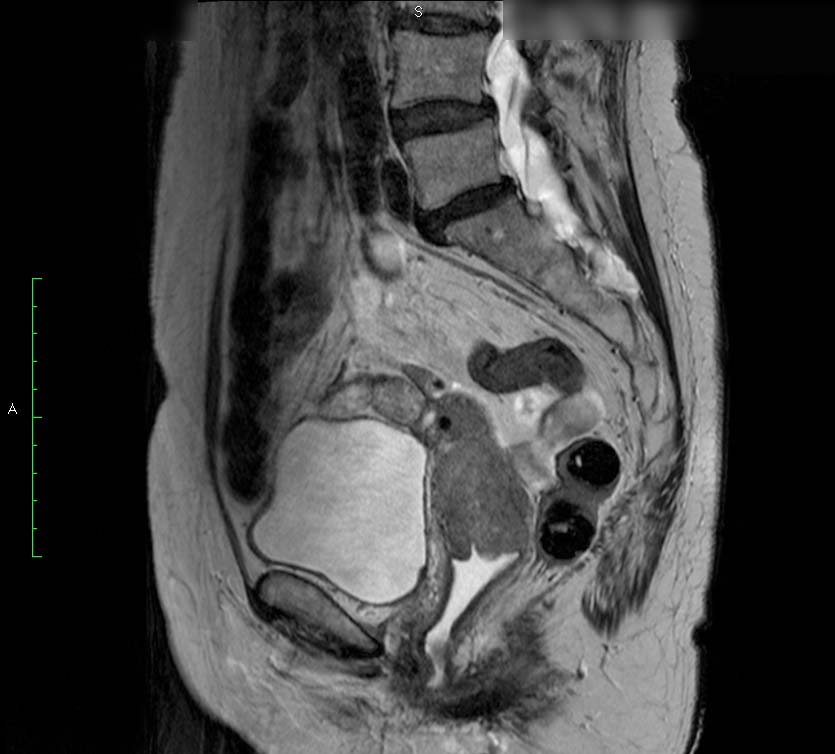

MRT-Untersuchung des weiblichen Beckens bei Malignomen

Die hochaufgelösste Magnetresonanztomographie (Kernspintomographie) des weiblichen Beckens bei 3 Tesla stellt derzeit die modernste bildgebende Diagnostik des weiblichen Beckens dar.

Eine Untersuchung der Gebärmutterhalses (Cervix), der Gebärmutterschleimhaut (Endometriums) oder der Eierstöcke (Ovarien) ist in einem 3Tesla MRT ist zu empfehlen, wenn ein unklarer Befund erhoben wurde oder vor einer Therapie, um diese der Ausbreitung der Tumors optimal anzupassen – z.B. Bestrahlung oder Operation.

MRT des weiblichen Beckens

Neben den hochaufgelössten Bildern wird mit Kontrastmittelgabe die Durchblutung des Tumors beurteilt. Hierdurch kann die Ausdehnung genau beurteilt werden und so die optimale Therapie geplant werden. Dies ist vor allem bei Endometriumskarzinomen sinnvoll.